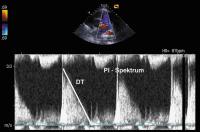

Abbildung 3: CW-Dopplerspektrum der Pulmonalinsuffizienz (PI): deutliches Pulmonalinsuffizienzspektrum mit auffallend steilem Kurvenabfall (Dezelerationszeit [DT]) als Ausdruck des niederen diastolischen PA-Drucks (hochgradige PI)

Keywords: CW-DopplerspektrumEchokardiogrammEchokardiographieEndokarditisHerzKardiologiePulmonalklappe